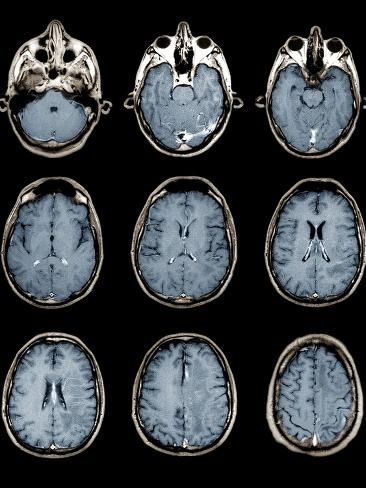

الأمر مثبت وتمت تجربته على الحيوانات وكانت نتائج مخيفه، تسببت باضرار عالية في ادمغة الفئران و تلف الخلايا والأعصاب

صار واضح ان لترددات المايكرويف علاقة بالقضية لانها اثبتت امكانيتها في التلاعب بالجسم والعقل البشري، وممكن نفسر إن هذا سلاح طاقة.. وذهبت أصابع الإتهام مباشرة إلى روسيا لأنه عدو للولايات المتحدة وغير مستبعد إن عندها الإمكانيات على صناعة أسلحة سرية بهذي الخطورة والتطور